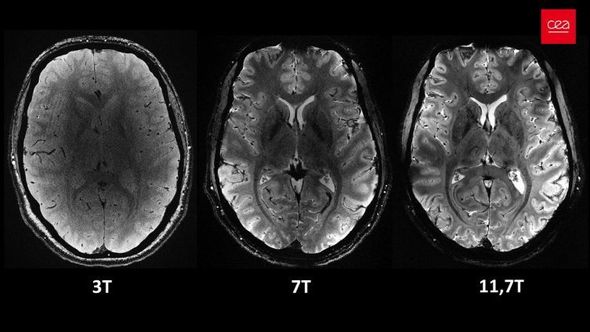

Açıqlamada qeyd olunub ki, 11,7 Tesla maqnit gücünə malik “Iseult” cihazı ilə qısa müddətdə çəkilən görüntüləri xəstəxanalarda istifadə edilən cihazlarla əldə etmək saatlar çəkə bilər.